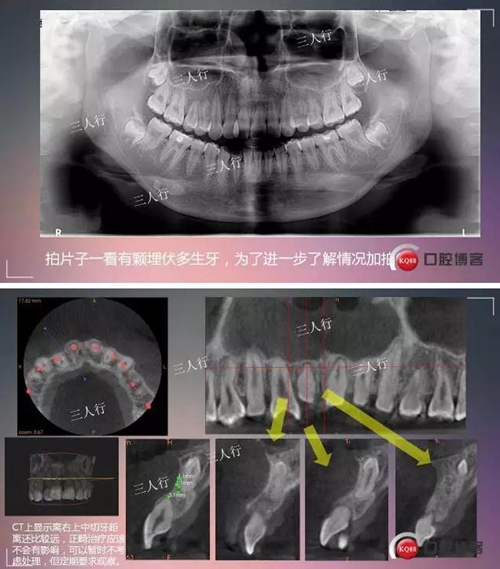

深部埋伏多生牙——微創(chuàng)處理